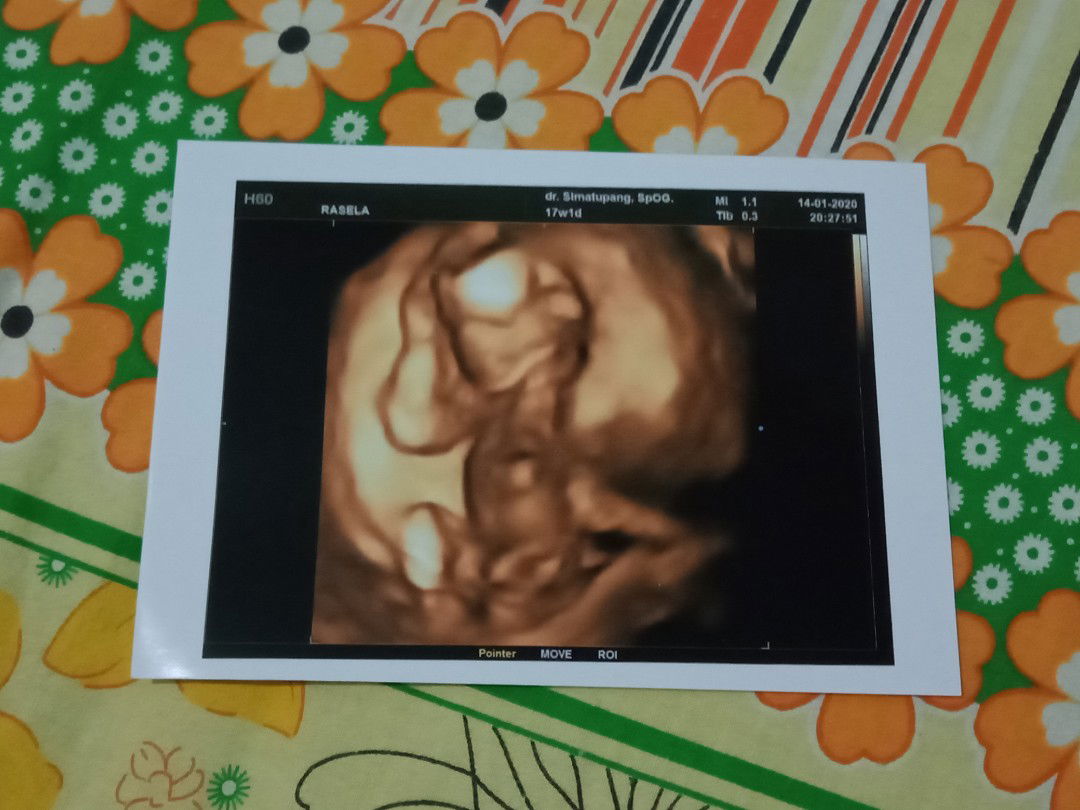

USG Rutin

Enggak bun, saya usg sebulan sekali, tapi pas TM 3 malah sebulan 2X, coz buat liat perkembangan bayi

Gak bener Bun. USG itu aman karna dia bukan alat sinar X kayak untuk ronsen gitu